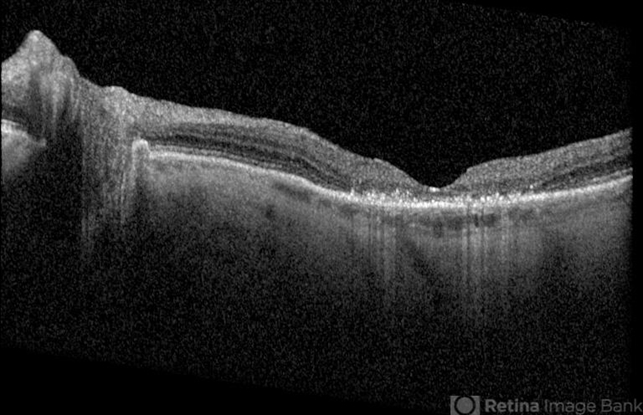

- Optical coherence tomography system

- Plaquenil toxicity